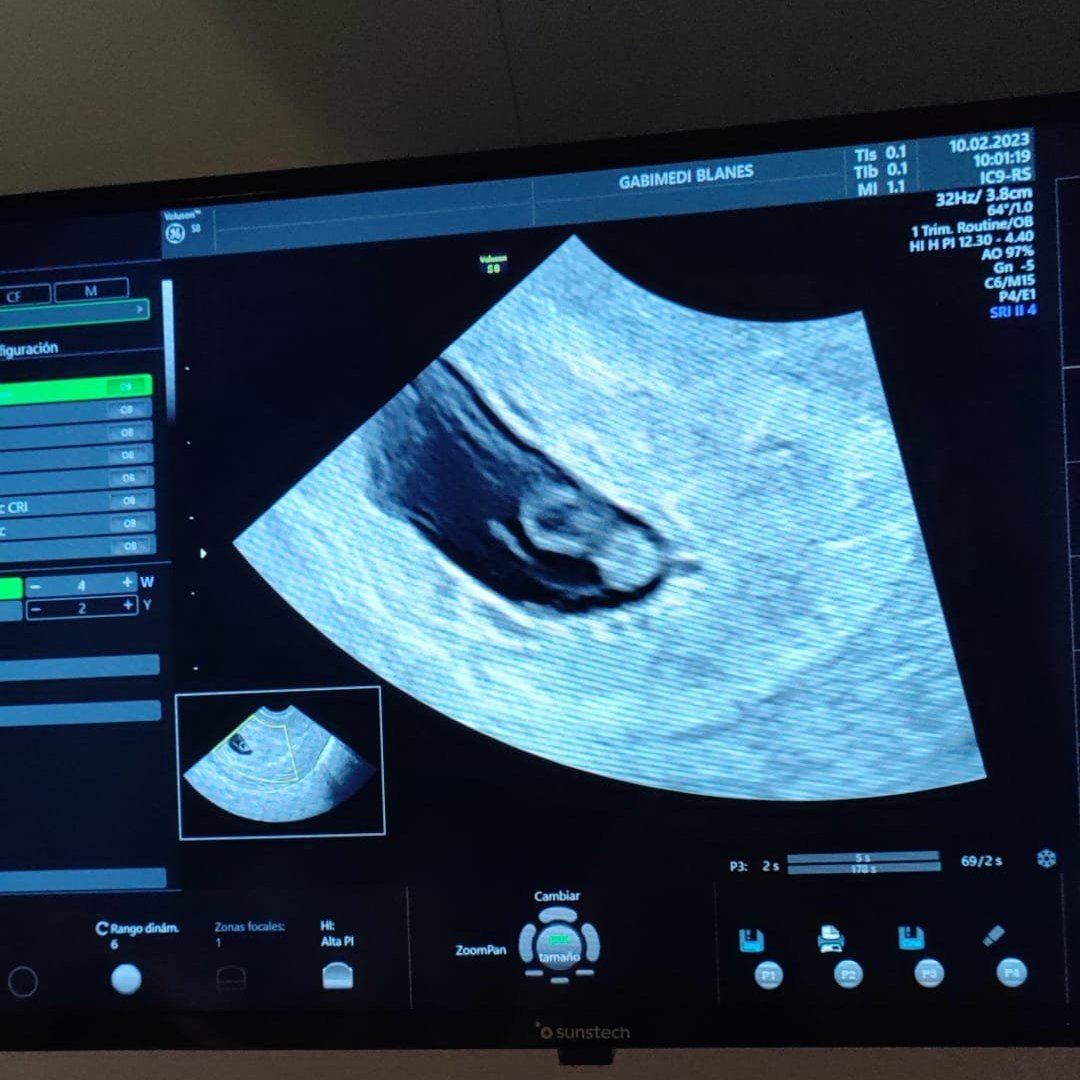

Бременна съм в 9+4 седмица. Но лекаря  ми каза че не отговаря на размерите било по малко от 9 седмици. Това ми е ясно щото съм с дълъг ме 40/45 дни със късна овулация. Но въпросът ми лекаря не ми каза на колко седмици отговаря бебока и ме викна д-р седмица понеже нямам търпение според вас коя седмица съм? Не живея в България и ми е трудно с езика от притеснение забравих да питам

Вероятно при него показва 8-ма. От снимката не се вижда как го изчислява апарата.

Не го пише никъде на снимката, но по развитието което виждам е 8-ма седмица.

благодаря Simple Smile дано всичко да е наред